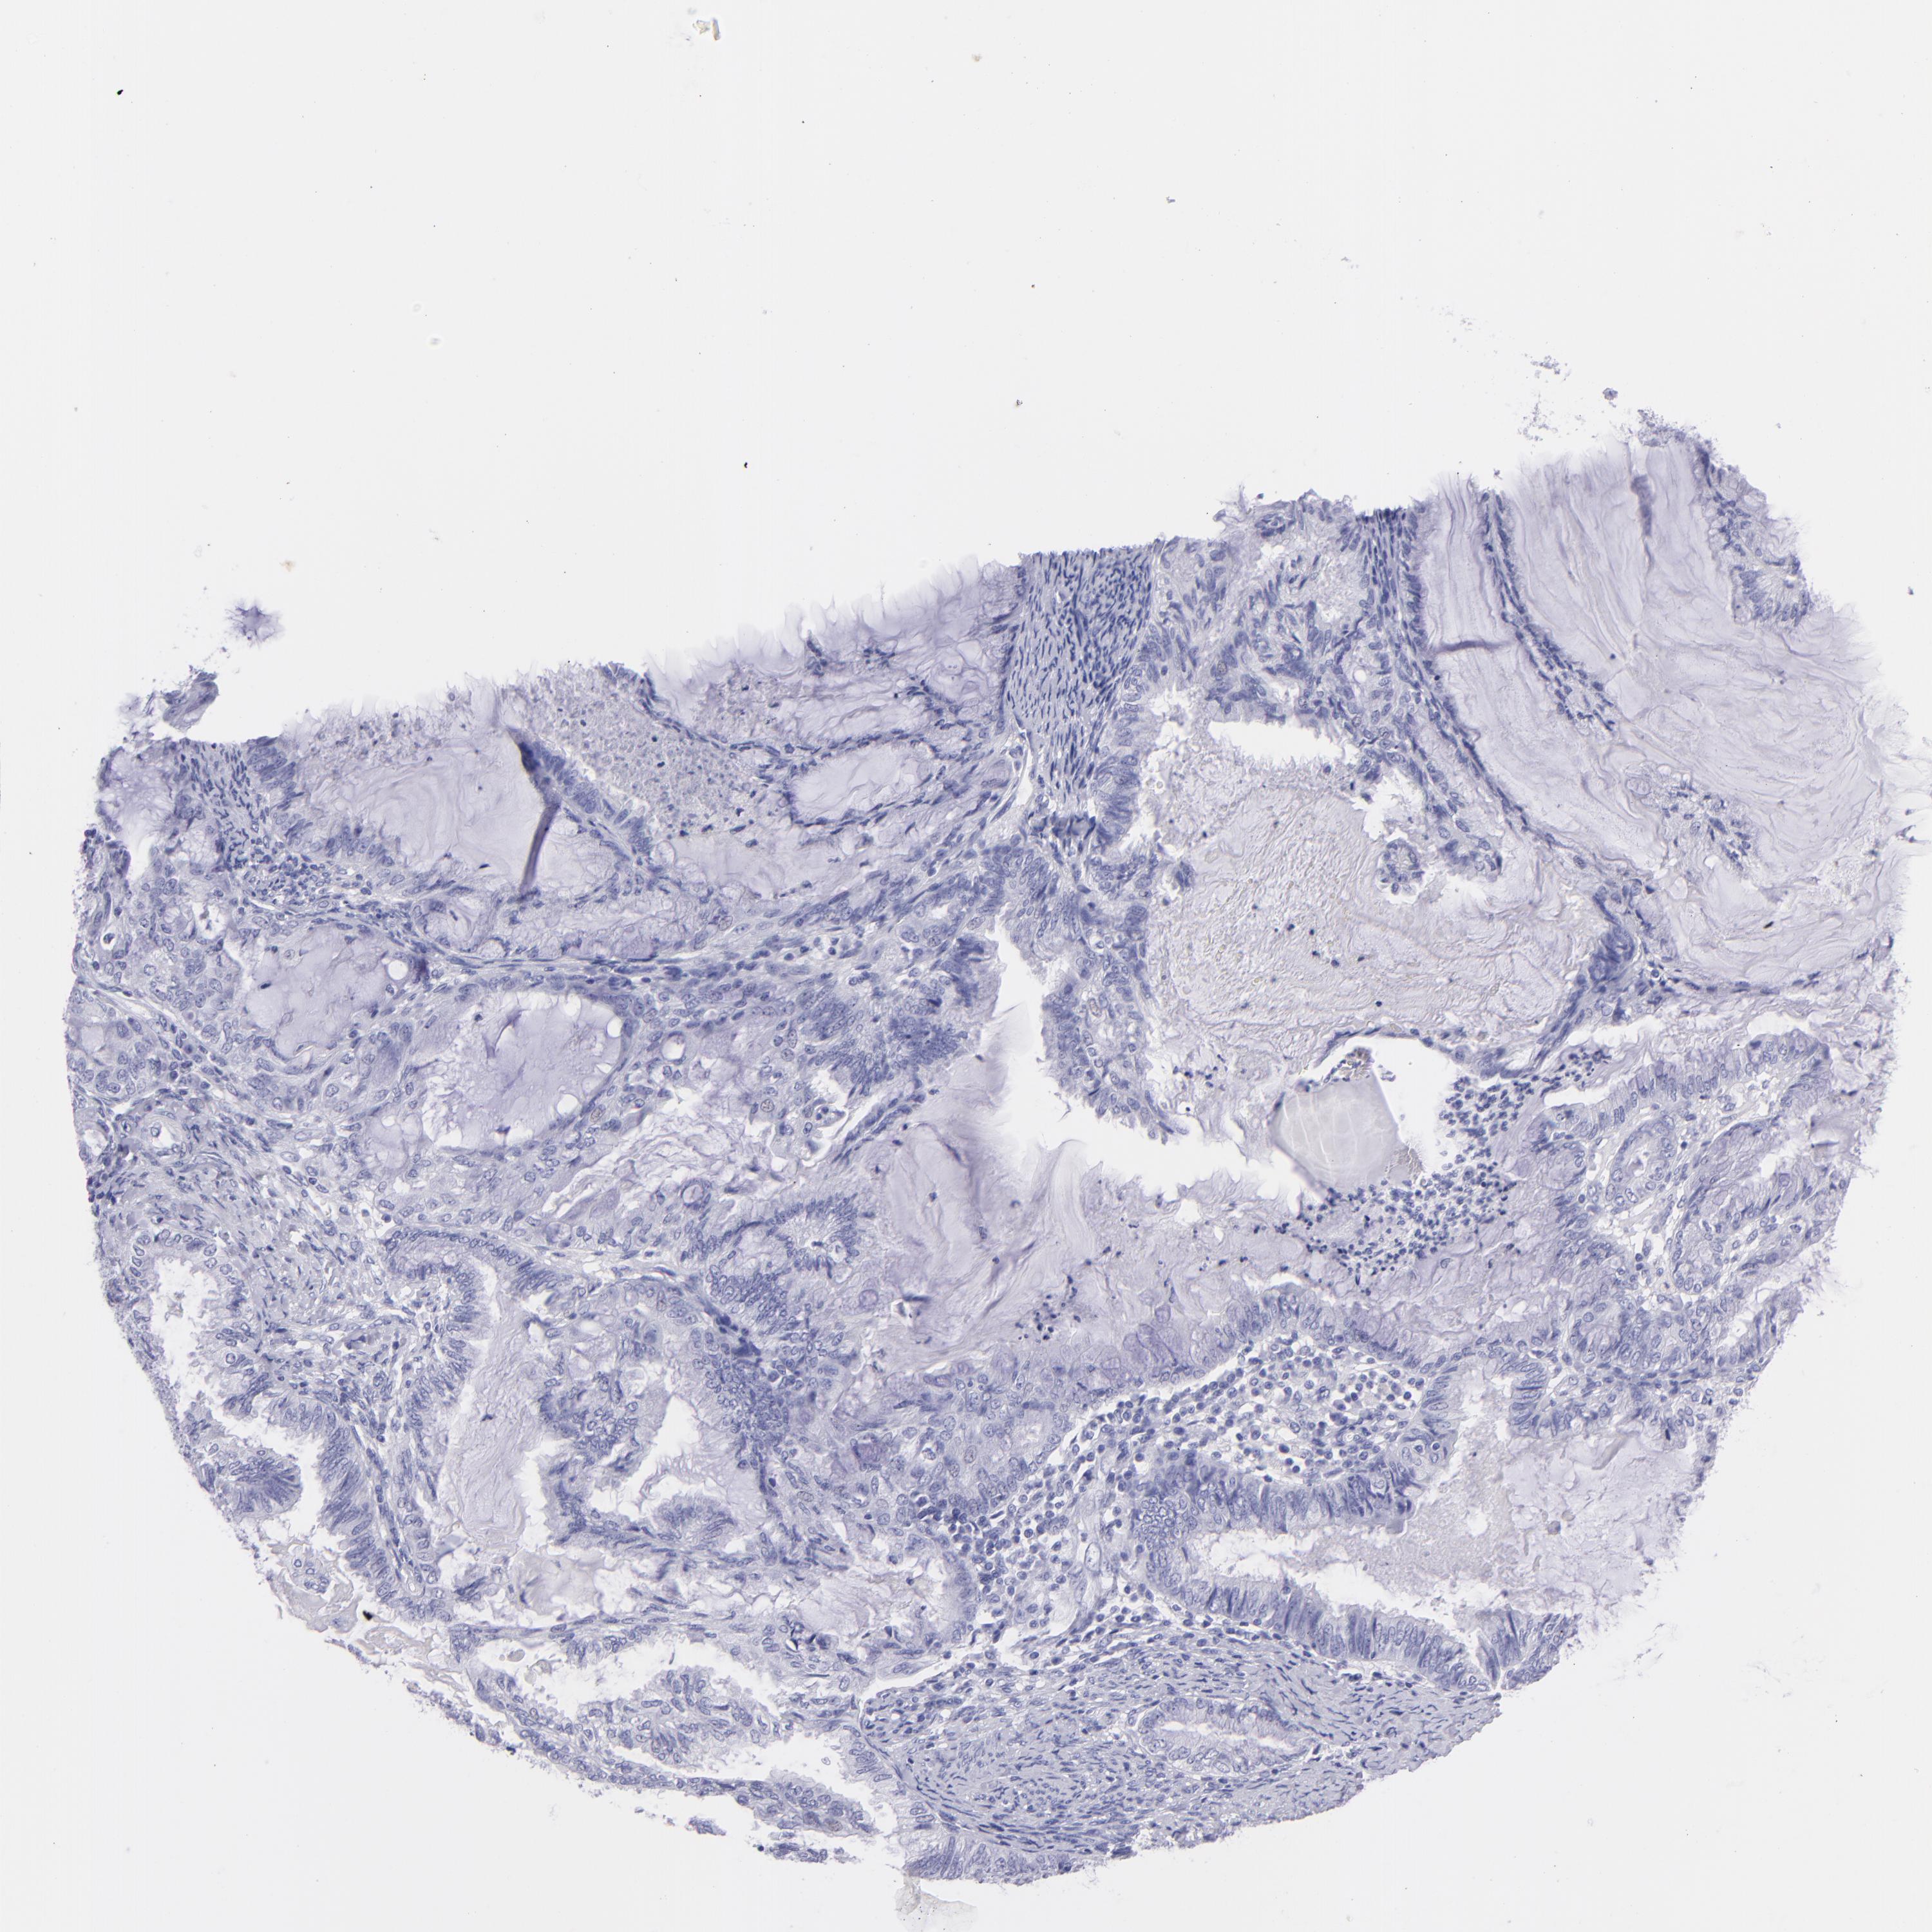

ENDOMETRIAL CANCER - Protein expressioni

A mouse-over function shows sample information and annotation data. Click on an image to view it in a full screen mode. Samples can be filtered based on level of antibody staining by selecting one or several of the following categories: high, medium, low and not detected. The assay and annotation is described here.

Note that samples used for immunohistochemistry by the Human Protein Atlas do not correspond to samples in the TCGA dataset.

Antibody stainingi

Antibody staining in the annotated cell types in the current human tissue is reported as not detected, low, medium, or high, based on conventional immunohistochemistry profiling in selected tissues. This score is based on the combination of the staining intensity and fraction of stained cells.

Each image is clickable and will lead to virtual microscopy that enables deeper exploration of all samples and also displays staining intensity scores, fraction scores and subcellular localization as well as patient and tissue information for each sample.

Adenocarcinoma, NOS

Adenoma, NOS

Adenocarcinoma, metastatic, NOS

Neoplasm, malignant, NOS